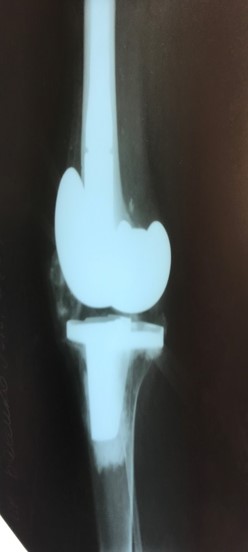

Приклад 3. Хвора К. 52 років. Діагноз: Деформівний IVст. гонартроз, стан після ТЕП лівого КС (2013р.). ІМТ хворої складає 35 балів. Асептична нестабільність компонентів ендопротеза лівого колінного суглоба, міграція великогомілкового компоненту (2017 р.) (рис. 2 а). Хворій виконано ревізійне ендопротезування: видалення компонентів ендопротезу, виявлений дефект медіального виростку великогомілкової кістки тип Т3А за класифікацією АОRI [G.A. Engh, C.H. Rorabeck, 1997]. Під час операції виконана кісткова пластика дефекту. Використаний ендопротез колінного суглоба з подовжувачами.